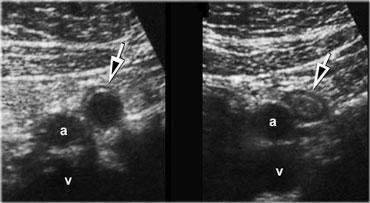

TRÁI: Tại góc phần tư trên phải phát hiện dày thành hành tá tràng. Có cả cấu hình khí xuyên thành và ngoài thành (mũi tên). Lớp mỡ viêm đại diện cho mỡ mạc treo và mạc nối (fat) đang cố gắng – nhưng vô ích – bao bọc lại vị trí thủng. PHẢI: Tại góc phần tư dưới phải phát hiện một lượng lớn dịch ổ bụng dạng mảnh vụn.

Hình bên trái là bệnh nhân bị thủng loét tá tràng.

Tại góc phần tư trên phải, quan sát thấy hình ảnh dày thành hành tá tràng.

Có cả cấu hình khí xuyên thành và ngoài thành (mũi tên).

Lớp mỡ viêm đại diện cho mỡ mạc treo và mạc nối (fat) đang cố gắng – nhưng vô ích – bao bọc lại vị trí thủng.

Tại góc phần tư dưới phải phát hiện một lượng lớn dịch ổ bụng dạng mảnh vụn (hình bên phải).

Trong loét dạ dày – tá tràng, siêu âm hiển thị hình ảnh dày thành tá tràng không đối xứng, trong đó có cấu hình khí cố định kéo dài từ lòng tá tràng đến ngoại vi thành hoặc thậm chí xâm nhập vào lớp mỡ viêm lân cận.

Trong trường hợp thủng, có thể phát hiện đường dẫn khí từ ổ loét vào khoang phúc mạc, thường theo hướng bụng hoặc đầu.

Khí tự do được hiển thị rõ nhất ở tư thế nằm nghiêng trái, nằm giữa gan và thành bụng phải.

Thường có nhiều dịch tự do chứa bọt khí và các mảnh thức ăn.